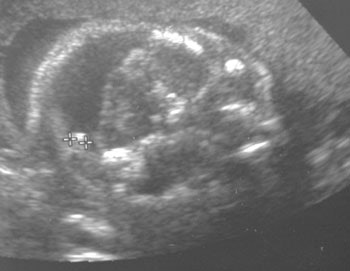

![]() |

un quiste con una calcificación posterior a la fosa posterior.

Imagen por gentileza de Dra. Deborah Levine.